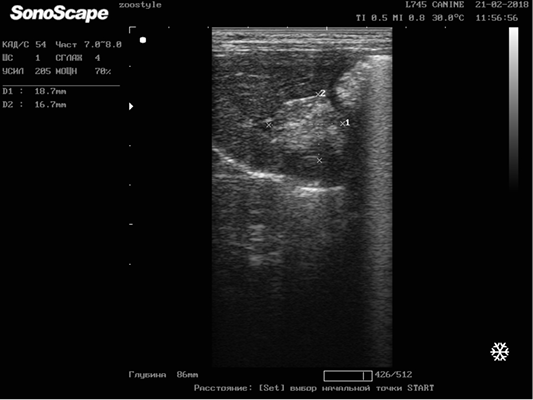

Figure 10

Longitudinal scanning of the mammary gland tumor (M5 region on the right side) on day 42 of the therapy (32.7х22.2 mm). Doggess, American Bulldog, at the age of 11.5 years.